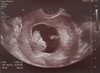

A teraz rośnie bąbelek dziś 9t2d. Wczoraj miałam wizytę u gina termin om zgodny z usg na 20.06.[emoji3] Dzidzia ma 2.40 cm serduszko bije 174bmp.[emoji7]

A i glukoza wyszła mi za dużo bo aż 106 [emoji853]zakaz jedzenia słodyczy owoców, soków masakra tych słodyczy to mogę nie jeść ale nie wiem jak sobie poradzę bez owocy[emoji37][emoji37] w tygodniu powtarzam glukozę i zobaczę co wyjdzie. Oto moja kruszynka.[emoji7] [emoji7] [emoji7]